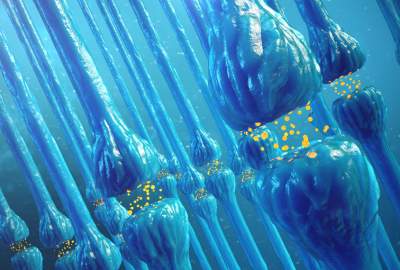

در حالی که موش مورد بررسی قرار می گرفت، محققان فعالیت نورون های خاص را در هیپوکامپ موش (ناحیه ای از مغز که در آن خاطرات جدید ایجاد می شوند) اندازه گیری کردند که برای رمزگذاری مکان ها شناخته شده است.

محققان برای بررسی چگونگی محو شدن خاطرات با گذشت زمان، موش ها را از این مسیر به مدت ۲۰ روز دور نگه داشتند. پس از این فاصله ی زمانی ۲۰ روزه، حافظه هایی که توسط تعداد بیشتری نورون رمزگذاری شده بودند، قوی تر بودند، بنابراین تست را به سرعت به خاطر می آوردند.

حتی اگر برخی از سلولهای عصبی فعالیت متفاوتی را نشان می دادند، هنگام تجزیه و تحلیل فعالیت گروههای بزرگی از نورونها، حافظه موش به وضوح قابل شناسایی بود. به عبارت دیگر، مغز با استفاده از گروه هایی از نورون ها، عملکرد خود را در حافظه و به خاطر سپردن اطلاعات، تقویت می کند، حتی اگر برخی از نورون ها، خاموش یا آسیب دیده باشند.

این مطالعه نشان می دهد که خاطرات ممکن است با افزایش سن، سریعتر از بین بروند. زیرا حافظه توسط تعداد بیشتری از نورونها رمزگذاری می شود و در صورت عدم موفقیت هر یک از این سلولهای عصبی، حافظه از بین می رود. این مطالعه نشان می دهد که یک روز، طراحی درمانهایی که می تواند باعث جذب بیشتر تعداد نورون ها برای رمزگذاری یک حافظه شود، می تواند به جلوگیری از، از دست دادن حافظه کمک کند.

نظریه های معمولی در مورد ذخیره سازی حافظه بر این اساس است که پایدار ماندن حافظه مستلزم تقویت اتصالات هر نورون منفرد است. نتایج ما نشان می دهد که افزایش تعداد نورون هایی که همان حافظه را رمزگذاری می کنند نیز باعث می شود حافظه برای مدت طولانی تری ادامه یابد. “

این مقاله با عنوان “Persistence of neuronal representations through time and damage in the hippocampus” می باشد.